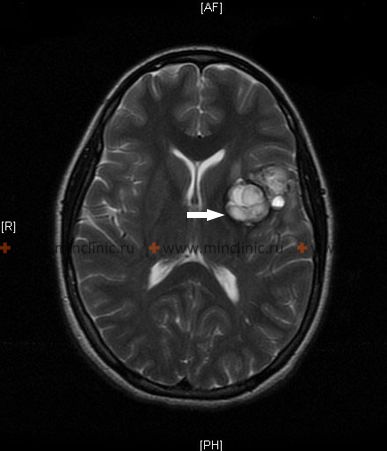

სისხლჩაქცევა თავის ტვინის სიმსივნეში

პირველად ან მეტასტაზურ თავის ტვინის სიმსივნეში უშუალოდ სისხლდენა (ინტრატუმორული სისხლჩაქცევა) ზოგჯერ შეიძლება იყოს საწყისი კლინიკური გამოვლინება, რომელიც იწვევს ინტრაცერებრული ნეოპლაზმის დიაგნოზს [1, 6]. თავის ტვინის სიმსივნეების გარკვეული ტიპები უფრო მეტად არიან მიდრეკილნი სისხლჩაქცევებისკენ, ვიდრე სხვები [6]. სისხლდენის შედარებით მაღალ რისკთან ასოცირებული ხშირი მეტასტაზური თავის ტვინის სიმსივნეები მოიცავს ქორიოკარცინომას, ავთვისებიან მელანომას, თირკმელუჯრედოვან კარცინომას და ფილტვის კიბოს გარკვეულ ტიპებს (ბრონქოგენური კარცინომა)[1, 6]. პირველად თავის ტვინის სიმსივნეებს შორის, გლიობლასტომა მულტიფორმე (ყველაზე გავრცელებული ავთვისებიანი პირველადი თავის ტვინის სიმსივნე მოზრდილებში) და, უფრო იშვიათად, მედულობლასტომა (ხშირი ავთვისებიანი თავის ტვინის სიმსივნე ბავშვებში, ტიპურად განლაგებული ნათხემში) ცნობილია, რომ ზოგჯერ ვლინდება ან უვითარდება ინტრატუმორული სისხლჩაქცევა[1, 6].